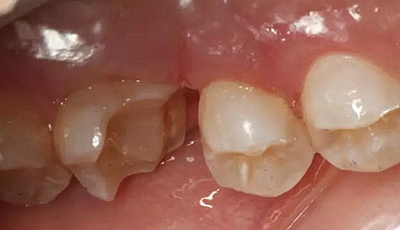

病例一 女性,20歲,大學(xué)生,要求補(bǔ)牙,檢查口內(nèi)可見A6大面積缺損,近中牙齦息肉,拍X片,根管充填物略差,但根周未見明顯陰影,口內(nèi)檢查無(wú)叩痛。建議患者冠延長(zhǎng)手術(shù)+高嵌體修復(fù)。

患牙遠(yuǎn)中邊緣嵴完整,強(qiáng)度沒(méi)有降低,故擬保留遠(yuǎn)中邊緣嵴,高嵌體修復(fù)。首先去除腐質(zhì)及原墊底材料,流體樹脂+3M Z350XT樹脂墊底。局麻下行冠延長(zhǎng)手術(shù)。在此需要提及個(gè)人的一個(gè)觀點(diǎn)。冠延長(zhǎng)手術(shù)原則上要求3-6個(gè)月以上才能永久修復(fù)。但是個(gè)人喜歡后牙肩臺(tái)建立在齦上,所以修復(fù)后的修復(fù)體邊緣位于牙齦上方1mm,對(duì)牙周的愈合影響較?。ㄈ绻麨辇l下邊緣則要慎重),故該患者術(shù)中按照齦上邊緣的設(shè)計(jì)進(jìn)行冠延長(zhǎng)手術(shù)。以下為術(shù)中: